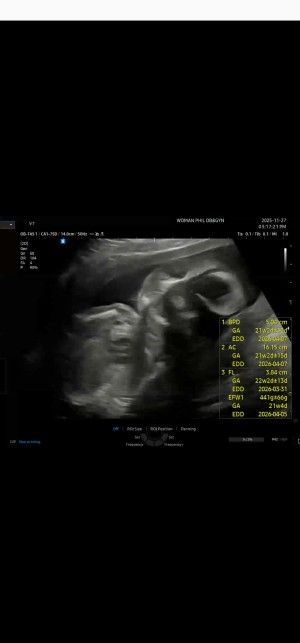

28주동안 엄마랑 잘 있어준 우리 아기

어느덧 임신 후기에 접어 들었다. 특별히 조심 하는 것도 없고, 입덧이 심하지 않아 못 먹는 것도 없었고, 많이 부족한 엄마인데 28 주 동안 엄마랑 잘 있 줘서 너무 고마워. 앞으로는 우리 말랑이를 위해 조금 더 조심하고 신경 쓰는 엄마가 될게! 건강하게 만나자 우리 말랑이 사랑해 :)